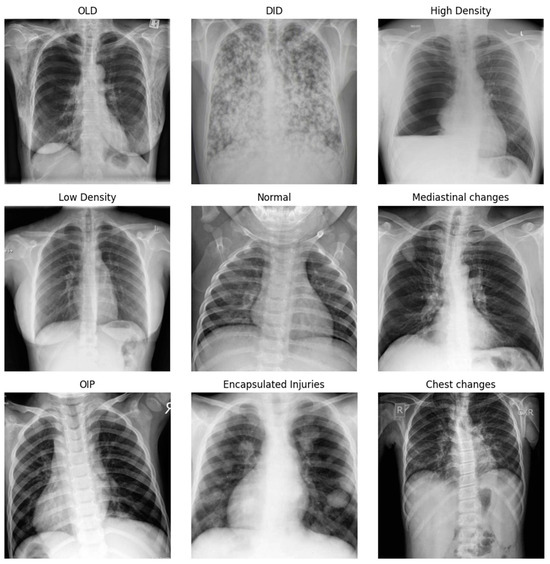

The dataset used in this study is the publicly available X-ray lung diseases dataset. The dataset consists of 9 classes, each representing a respiratory system disease which can be seen in Figure 1.

Figure 1.

X-ray lung diseases dataset based on the category of the disease.

These diseases include obstructive pulmonary diseases (OLD), degenerative infectious diseases (DID), higher and lower density diseases, encapsulated lesions, mediastinal changes, chest changes, obstructive inflammatory processes (OIP), in addition to the normal case distributed over 6753 images. The dataset is lightly imbalanced (See Figure 2) and contains images of inconsistent dimensions. For training purposes, all images were resized to a 384 × 384 resolution.